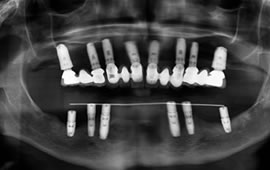

Being able to fabricate an implant retained upper or lower bridge was only a dream a few years back regaining taste and ability to chew without fear are major achievements not to mention being able to maintain teeth as if they were your own. Difficult to phathom but true these days. If you are tired of denture adhesives and wish to explore your possibilities, please do not hesitate to contact us or send your x-rays via email.

See photos of a complete dental implant case